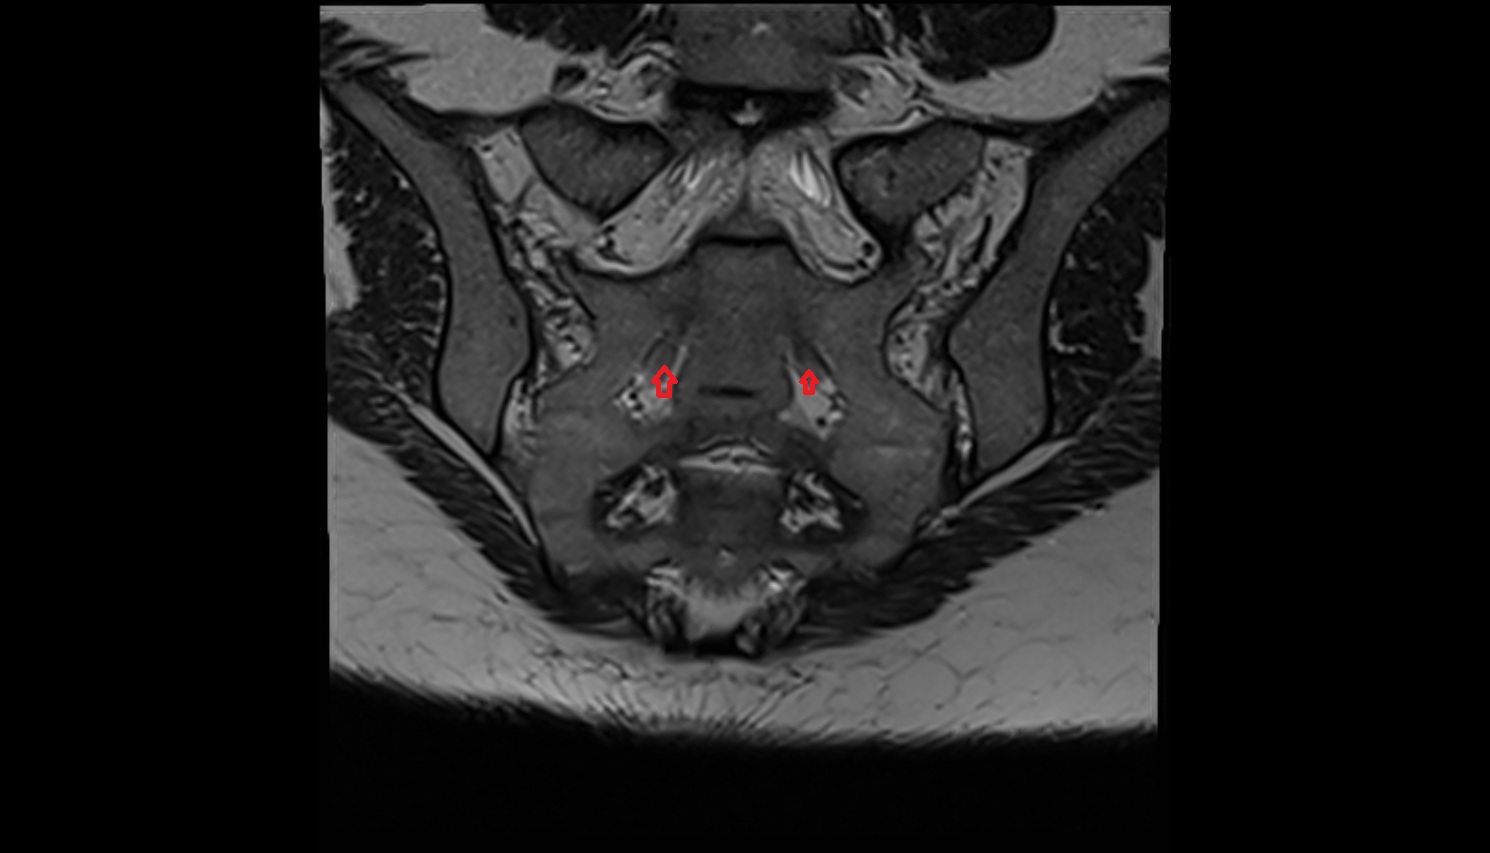

- Sacroiliac joint

- Anterior sacroiliac ligament

- Interosseous sacroiliac ligament

- Posterior sacroiliac ligament